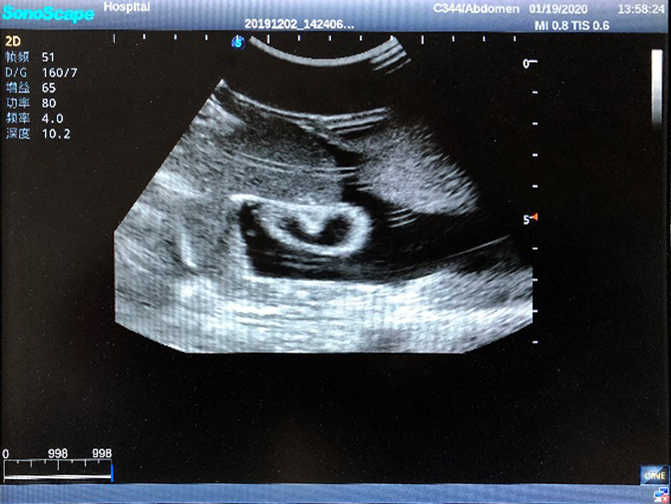

Abdominal Ultrasound Phantom

Model TYE1569

Outline

This product is a true-to-life male torso designed for abdominal ultrasound training. It offers you an effective solution for preparing learners for routine abdomen checkup including percussion, various puncture under ultrasound guidance and ultrasound image reading. The realism of the product and the skillset specific to abdominal examination techniques will bring learners competence and confidence.

2)  High quality ultrasound image with clear structures like gallbladder, liver, intestines, arteries and veins etc.

4)  ltrasound gallbladder pathologies like cholecystitis, gallstone and polypoid degeneration

5)  Normal & pathological ultrasound live and intestine models inside